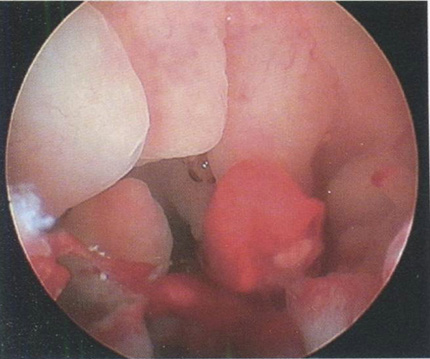

Рис. 3.2. Заключение гистероскопии: гиперплазия эндометрия.

Гистологическое исследование: простая железистая ГПЭ.